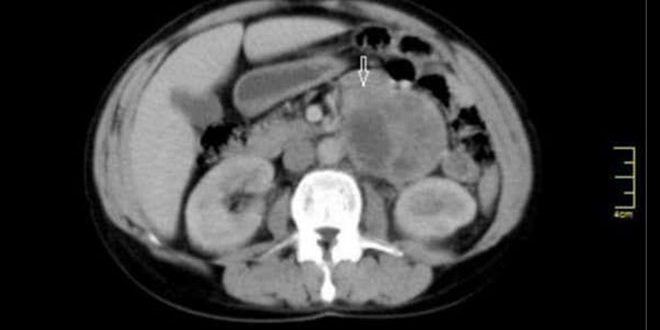

دكتور الجراحة العامة شوقي محمود الذي أجرى العملية بمساعدة طاقم طبي مختص قدم شرحاً تفصيلياً عن مجرياته قائلاً إنه عبارة عن استئصال كتلة ورمية من النوع النادر الحدوث داخل البطن لمريضة تبلغ من العمر 41 عاما تعاني من انزعاج بمنطقة الخاصرة اليسرى من البطن سبق وأن تم تشخيص ورم لها بنحو 2 سم لم تتم معالجته في حينها لتعاني بعدها على مدى ثلاث سنوات من نوبات صداع وأحيانا قلق مترافقة مع تسرع بضربات القلب ولم تذكر وجود ارتفاع توتر شرياني ما جعلنا نتعامل مع الحالة على أنها كتلة مجهولة المنشأ.

وأشار محمود إلى أنه بعد إجراء الفحوص المخبرية والشعاعية للمريضة وبعد تشخيص الورم بإجراء التلوينات المناعية النسيجية والتحضير الداوئي لها تم إجراء العمل الجراحي الذي استمر لنحو خمس ساعات ونصف الساعة لافتا إلى المضاعفات الخطيرة التي رافقت العمل الجراحي لناحية الارتفاع والانخفاض الكبير والمفاجئ للتوتر الشرياني والتسرع الشديد بنبضات القلب نتيجة ملامسة الكتلة الورمية مما استدعى إجراءه دون ملامسة الورم وهي حالة خطرة جداً تواجه طبيب الجراحة والتخدير في أثناء العمل الجراحي وتهدد بحدوث اضطراب نظم القلب أو حوادث دماغية وعائية للمريض بالإضافة إلى حدوث نزيف عند المريضة تجاوز 2 ليتر من الدم ما استدعى نقل 6 وحدات دم لها إضافة إلى خسارتها كمية كبيرة من السوائل.

بدوره قدم اختصاصي التشريح المرضي الدكتور حسام سلمان شرحا للمراحل التي مرت بها الحالة التشخيصية للكتلة ضمن مخبر التشريح في شعبة التشريح المرضي الموجودة بالمشفى بعد استئصالها حيث تم أخذ مقاطع نسيجية ومن ثم تجهيزها على شرائح زجاجية للتشخيص لافتاً الى أن حجم الكتلة يبلغ 9 سم وأجريت لها الاختبارات اللازمة ليتبين أنها من نوع باراغانغليوما مناعية مؤكداً أن الخباثة بهذا النوع لا تكتشف الا بالانتقالات فقط.